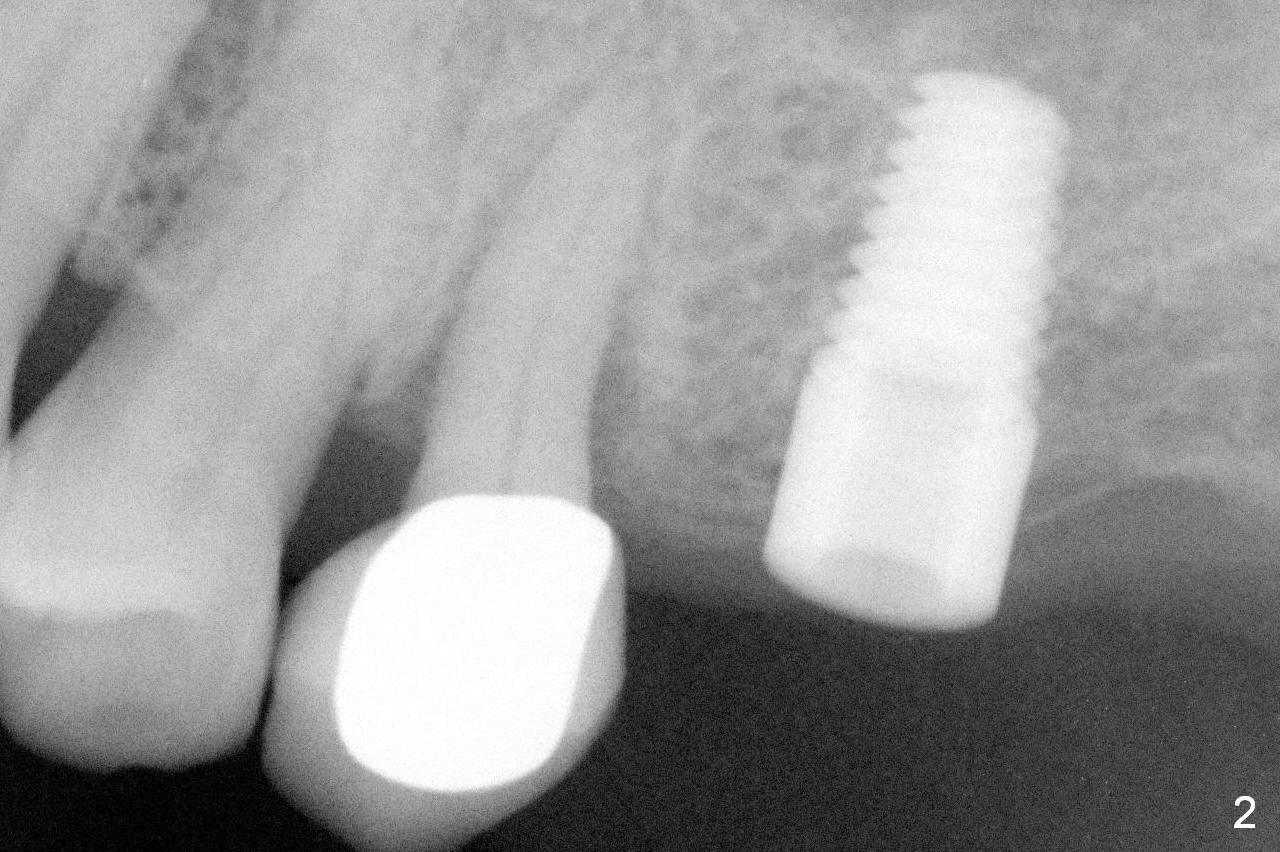

A 73-year-old woman is a possible bruxer with partial edentulism; the tooth #13 had increased periodontal ligament (pdl) space 4 years ago (Fig.1 *). A 5x14 mm tissue-level implant is placed at the site of #14 (Fig.2). The implant appears to be osteointegrated in 6 months (Fig.3). There is crestal bone loss 8 months post cementation (Fig.4 *). The persistent increased pdl at #13 is most likely associated with occlusal tramua from the tooth #19 (Fig.5 (13 months post cementation of #14)). Three years post #14 cementation, the tooth #13 has mobililty II (Fig.6); bone density increases around the apical half of the implant (arrowheads). Normally bone density is the highest coronally where functionality dictates. This indicates the bone loss is getting worse at #14 as well.